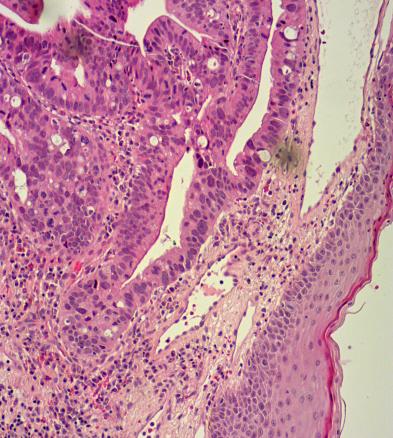

Les principaux diagnostics différentiels sont la thrombose hémorroïdaire externe, le prolapsus hémorroïdaire -interne, la marisque hypertrophique et le carcinome épidermoïde en cas de nodule. En cas de maladie de Paget, ce sont le psoriasis, les mycoses, l’eczéma de contact, les -dermites d’irritation, le lichen plan ou scléro-atrophique et la  maladie de Bowen. Le diagnostic formel nécessite une analyse histologique (fig. 2).

L’adénocarcinome de l’anus est un cancer rare (moins de 10 % des cancers de l’anus). Il apparaît le plus souvent au niveau de l’épithélium glandulaire ou des glandes du canal anal, plus rarement au niveau de la peau périanale. Une fistule anale chronique et la maladie de Crohn sont des facteurs favorisants.

La maladie de Paget est un cas particulier, pouvant être « primitive » ou « secondaire » à l’extension de contiguïté d’un carcinome du canal anal ou de la vulve ou à la propagation à l’anus d’un cancer viscéral synchrone distant, notamment colorectal, urogénital, mammaire ou nasopharyngé.